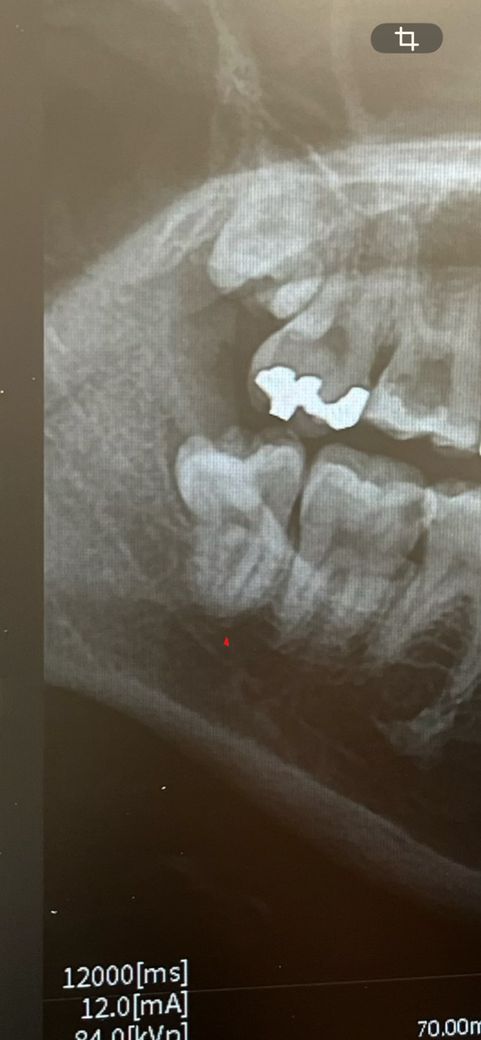

하악 사랑니 뽑으려고 하는데 매복은 아닌 거 같고.. 이런 게 반매복인가요?

수험생이라 회복이 빨라야 하는데 사진상으로 봤을 때 이런 사랑니는 며칠 정도면 회복되나요?

1. 부분매복사랑니입니다

2. 발치 후 컨디션 회복은 사람마다, 케이스마다 다 다릅니다

3. 보통 3~4일 정도 후부터 정상적으로 식사하시고, 1주일 정도부터 정상 생활로 회복기간 잡습니다. 그 이후로도 2~3개월에 걸쳐 잇몸과 잇몸뼈가 아물게 됩니다